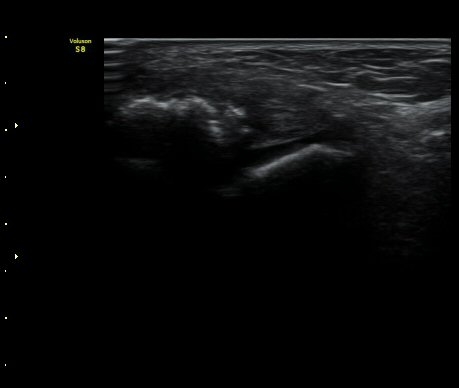

3ÁÖ ÈÄ ÃßÀû°Ë»ç»ó °üÀý³» ºÎÁ¾ÀÌ ¼Ò½ÇµÇ°í(±×¸² 4). Àü°Å°ñºñ°ñÀδëÀÇ Àú¿¡ÄÚ ºÎÁ¾ÀÌ

°¨¼ÒÇÏ°í °ß¿­°ñÀý °ñÆíÀº ºñ°ñ °¡±îÀÌ À§Ä¡Çϰí ÀÖ´Ù(±×¸² 5, 6).

ÃÊÀ½ÆÄ Åõ½ÃÇÏ ºÎÇϰ˻翡¼­ ºñ°ñ°ú ÀδëºÎÂøºÎ¿Í  ºñ°ñ°ú °Å°ñ»çÀ̰¡ ¹ú¾îÁöÁö ¾Ê´Â´Ù

(樨毢 2).